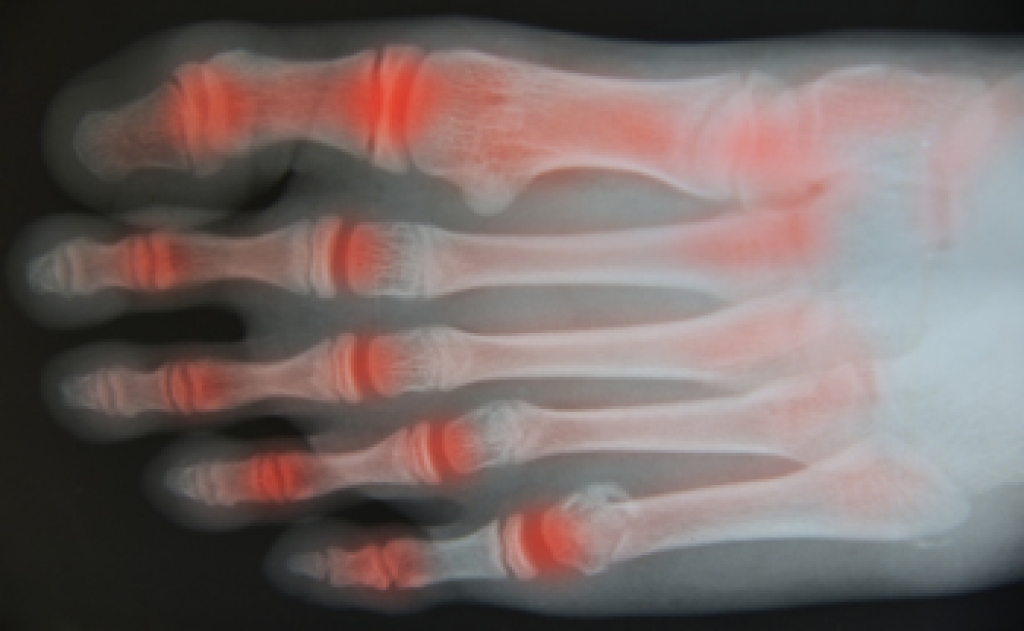

In order to diagnose your bunion, your podiatrist may ask about your medical history, symptoms, and general health. Your doctor might also order an x-ray to take a closer look at your feet. Nonsurgical treatment options include orthotics, padding, icing, changes in footwear, and medication. If nonsurgical treatments don’t alleviate your bunion pain, surgery may be necessary.

Arthritis That Can Take a Toll on the Ankles

The ankle joint carries the body’s weight with every step, making it vulnerable when arthritis sets in. One common type is osteoarthritis, which develops gradually as cartilage wears down over time, leading to stiffness and pain. Rheumatoid arthritis is another, caused by the immune system attacking the joint lining, often affecting both ankles at once and causing swelling and deformity. Post-traumatic arthritis can appear years after an ankle injury, such as a fracture or severe sprain, as damaged cartilage breaks down earlier than normal. Less commonly, gout targets the ankle when uric acid crystals build up, triggering sudden, sharp pain and redness. Each form of arthritis may affect the ankle differently, but all can reduce mobility and interfere with daily life. If you have any kind of ankle pain, it is suggested that you schedule an appointment with a podiatrist for a proper diagnosis and appropriate care.

Arthritic Foot Care

Arthritis is a term that is commonly used to describe joint pain.  The condition itself can occur to anyone of any age, race, or gender, and there are over 100 types of it.  Nevertheless, arthritis is more commonly found in women compared to men, and it is also more prevalent in those who are overweight. The causes of arthritis vary depending on which type of arthritis you have. Osteoarthritis for example, is often caused by injury, while rheumatoid arthritis is caused by a misdirected immune system.